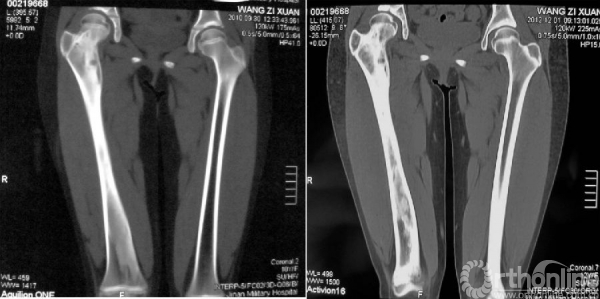

本病女性多见,男女发病率约为1.2:3,多在10岁左右发病,主要症状为轻微疼痛,局部肿胀及压痛。因症状轻微往往被忽略,多数病例是在以后查体或发生病理骨折时才被发现,骨折时疼痛可突然加重,肢体功能障碍,但骨折很少移位(图1),由于受累骨的坚固性受到明显影响,肢体可出现弯曲畸形,发生于股骨近端的常形成髋内翻,被称为“牧羊拐畸形”(图2)。

图1 股骨病理性骨折,没有明显的移位